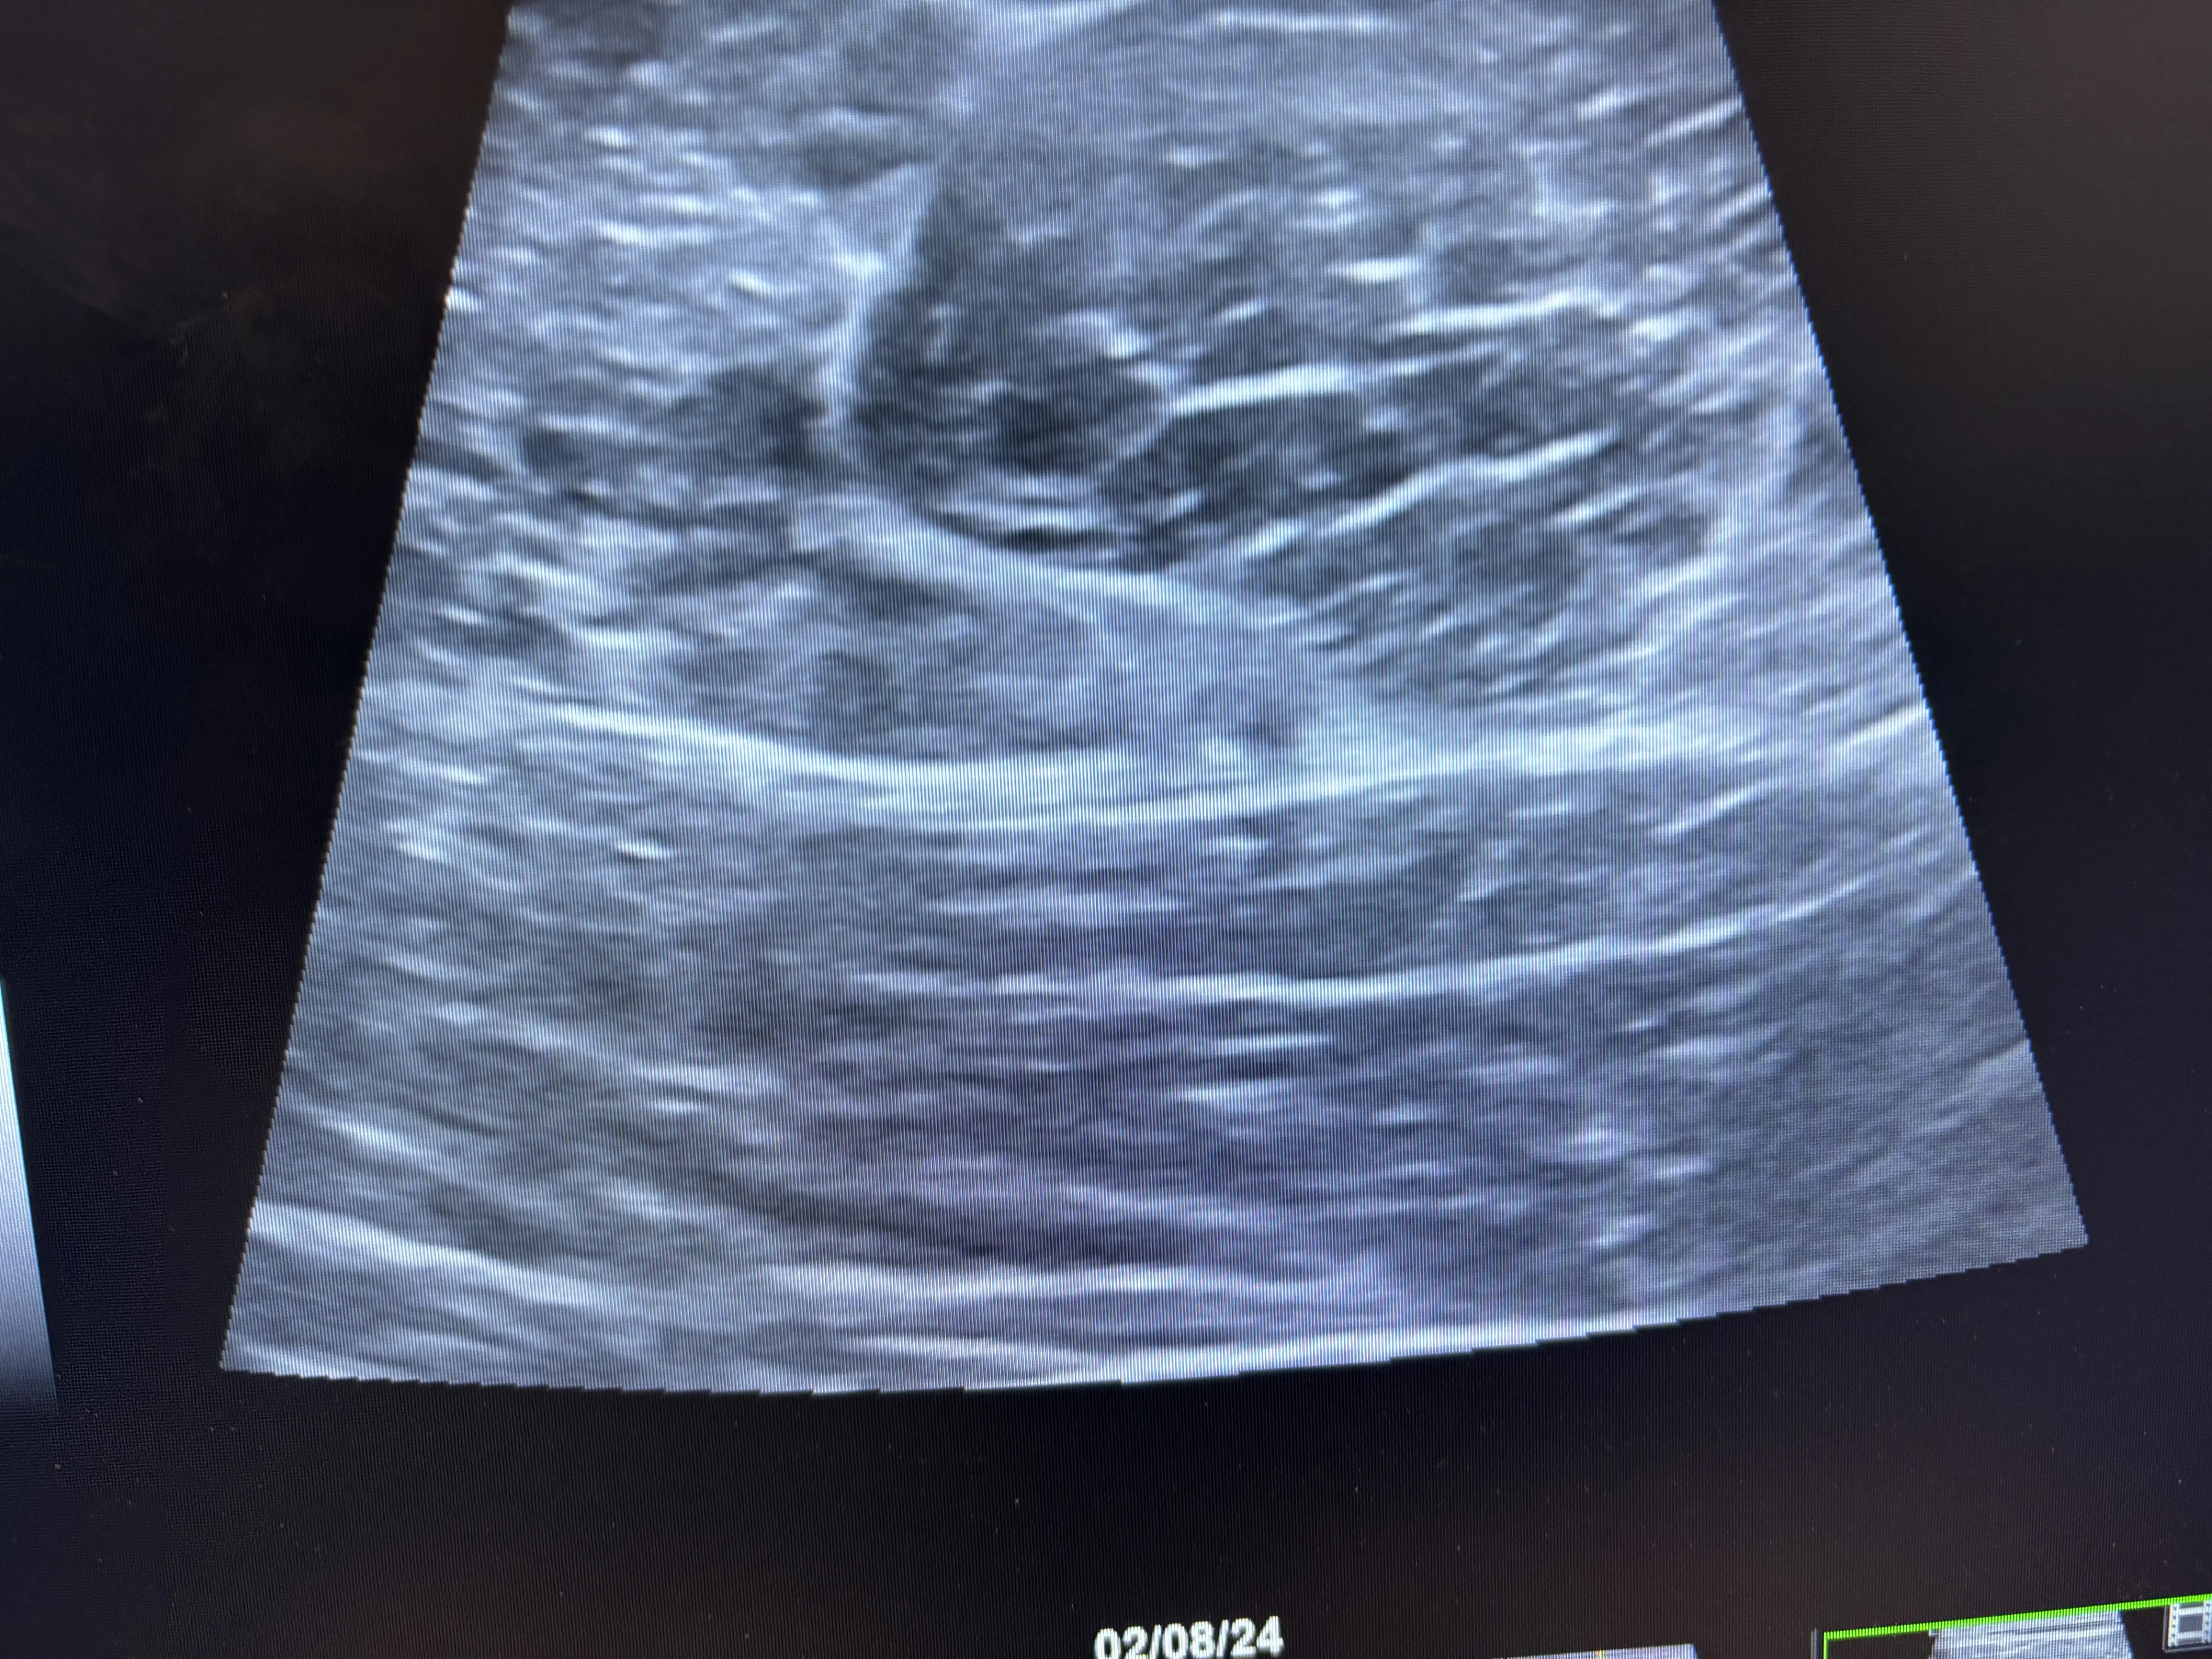

Boston Sports & Biologics is a multidisciplinary orthopedic practice that focuses on non‑surgical, minimally invasive treatment of acute and chronic musculoskeletal injuries. The clinic leverages high‑resolution diagnostic musculoskeletal ultrasound to accurately diagnose tendon, ligament, nerve, and joint pathology, allowing for precise, ultrasound‑guided therapeutic interventions. Their approach emphasizes personalized care plans that target the underlying cause of pain rather than merely addressing symptoms, with the goal of restoring function while avoiding traditional orthopedic surgery. The practice offers a comprehensive suite of regenerative and orthobiologic therapies, including platelet‑rich plasma, bone‑marrow concentrate, micro‑fragmented adipose tissue (Lipogems), stem‑cell‑derived treatments, and hyaluronic‑acid viscosupplementation. These biologic options are complemented by percutaneous tenotomy (Tenex), nerve hydrodissection, trigger‑point injections, shockwave therapy, and prolotherapy, all performed under ultrasound guidance to maximize accuracy and safety. The team also provides ultrasound‑guided carpal‑tunnel and trigger‑finger releases, as well as peripheral joint and soft‑tissue injections. Founders Dr. Walter Sussman and Dr. Erek Latzka are dual board‑certified physicians in Physical Medicine & Rehabilitation and Sports Medicine, with extensive clinical, research, and teaching experience in ultrasound‑guided procedures and regenerative medicine. Their combined expertise, supported by academic affiliations with Tufts University and the University of New England, positions the practice as a leader in innovative musculoskeletal care throughout New England.